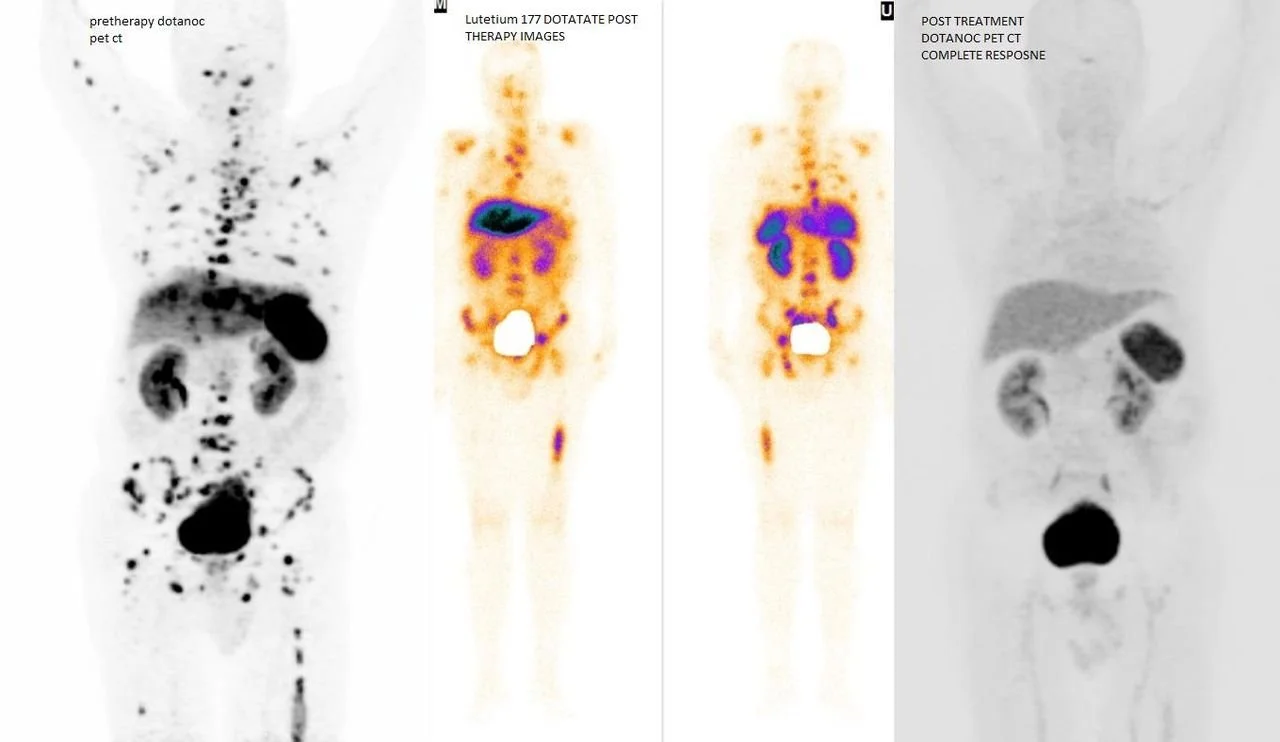

Lutathera es una terapia con radionúclidos dirigida al tratamiento de tumores neuroendocrinos (TNE) del tracto gastrointestinal y páncreas. Combina Lutecio-177 con DOTATATE, que se une a los receptores de somatostatina presentes en este tipo de tumores, permitiendo administrar radiación precisa para destruir células tumorales.

Con Lutathera se consigue:

Mejor control de los tumores neuroendocrinos avanzados

Aumento en la supervivencia y mejoría de la calidad de vida

Tratamiento eficaz cuando otras opciones ya no son suficientes